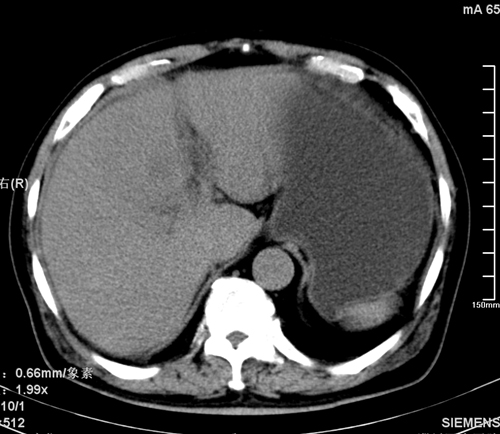

以下是引用liaoqiang在2008-3-27 15:57:00的发言:[br]1右肾脏周多发大小不一球形影,考虑肾脏囊肿可能性大。2胆囊边界欠清楚。考虑胆囊炎可能性。

以下是引用随光逐影在2008-3-27 16:33:00的发言:[br]考虑为:1)双肾囊肿可能。2)急性胆囊炎。建议:行进一步检查。